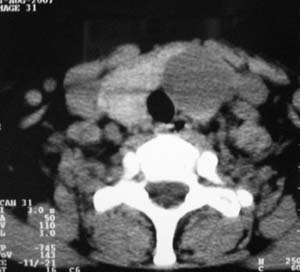

以下是引用zsl6918在2007-8-27 14:40:00的发言:[br]双侧甲状腺多发性低密度占位,边界清晰,密度欠均匀,尤以左侧明显,与周围组织分解清,考虑多发性腺瘤可能性大,不除外结节性甲状腺肿

以下是引用liaizhi在2007-8-27 15:20:00的发言:[br]双侧甲状腺散在多个囊性第密度影,左侧最大一个病灶与正常甲状腺分界尚可,气管受压稍右移。考虑甲状腺瘤的可能性大。